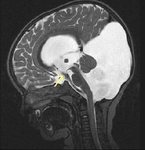

Hidrosefali tedavi edilmezse, beyin omurilik sıvısının (BOS) birikmesi nedeniyle beyin dokusunda baskı oluşur ve bu durum çeşitli komplikasyonlara yol açabilir. Uzun vadede, hidrosefali ciddi nörolojik sorunlara neden olabilir. Bunlar arasında motor fonksiyon bozuklukları, yürüyüş problemleri, denge kaybı, görme ve işitme sorunları, bilişsel gerileme ve hafıza kaybı sayılabilir. Ayrıca, hastanın yaşam kalitesi önemli ölçüde düşebilir; günlük aktivitelerini yerine getirme yeteneğinde azalma, sürekli baş ağrıları, bulantı ve yorgunluk gibi belirtiler ortaya çıkabilir.